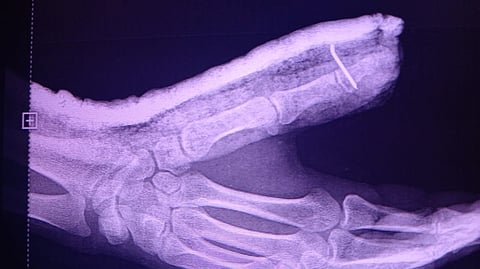

وأوضح تجمع المدينة المنورة الصحي، أن المستفيد في العقد الثالث من العمر من الجنسية الليتوانية، قد حضر إلى قسم الطوارئ بمستشفى الأمير عبدالمحسن عن طريق الإسعاف الخاص، وبعد إجراء الفحوصات الطبية اللازمة من قِبَل الطاقم الطبي بالتعاون مع الفريق الأمريكي MGB؛ تَبين وجود كسر مفتوح في سلامية الإبهام لليد اليسرى مع وجود قَطع في وتر الإبهام الباسط.

وأضاف التجمع أنه على الفور قرر الفريق الطبي إجراء عملية جراحية لتثبيت الكسر وإصلاح الوتر؛ حيث تكللت العملية بنجاح -ولله الحمد- وغادر المريض المستشفى بعد استكمال الفترة العلاجية اللازمة وهو بحالة صحية جيدة.